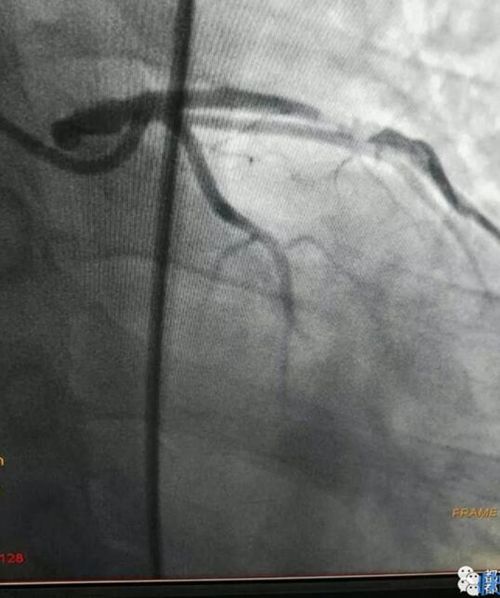

梁毅、葉興、戴瑞醫(yī)生和導管室的護士、技師們密切協(xié)作,以最快的速度完成經(jīng)右股動脈的冠狀動脈造影,發(fā)現(xiàn)有一塊血栓堵在了李先生冠狀動脈前降支近段的血管上,同時發(fā)現(xiàn)這段血管99%狹窄,立即予以植入支架并及時抽吸及局部藥物注入,恢復了前向血流,有效終止了電風暴的發(fā)作。

栓塞的血管造影